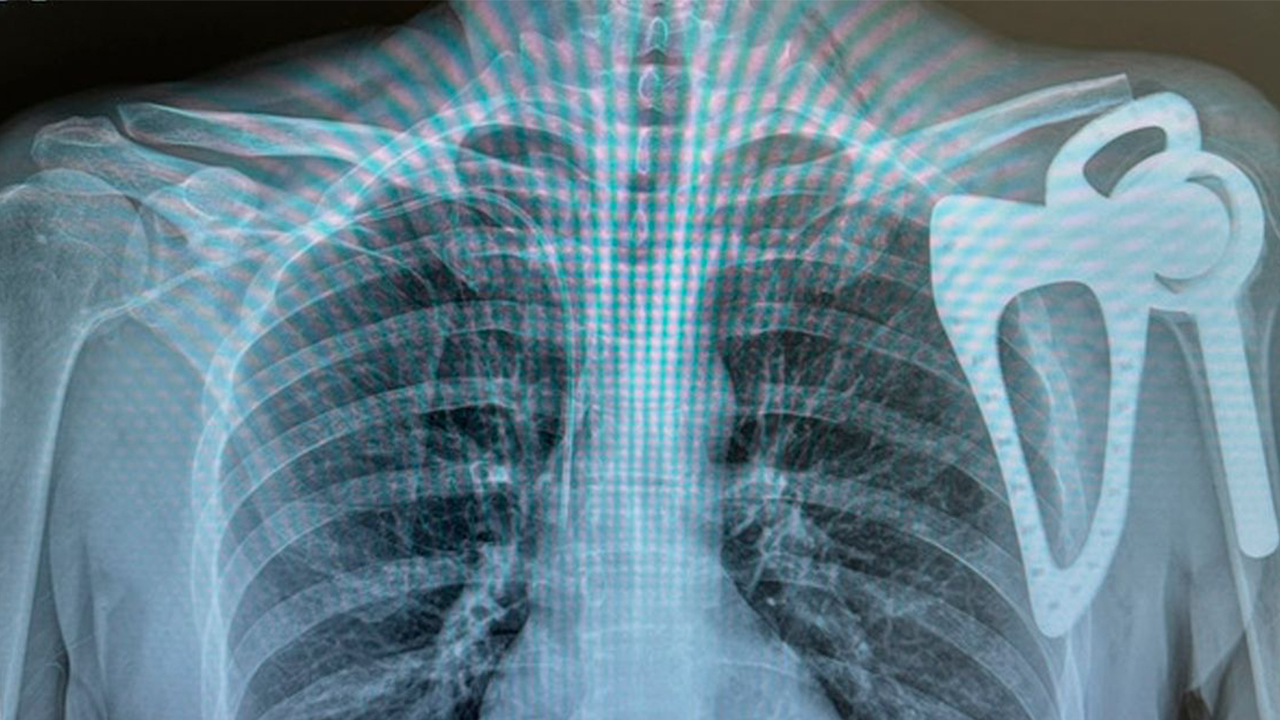

João Paulo Freitas e a sua equipa realizaram uma escapulectomia total (procedimento cirúrgico no qual a omoplata é completamente removida) e a reconstrução da omoplata e da articulação do ombro esquerdo de um homem de 48 anos com um tumor ósseo na omoplata.

A intervenção foi realizada com recurso a uma prótese custom made de omoplata total, já utilizada noutros países, mas aplicada pela primeira vez em Portugal, revela a MBA Surgical Empowerment, empresa responsável pelo fabrico de materiais para uso médico.